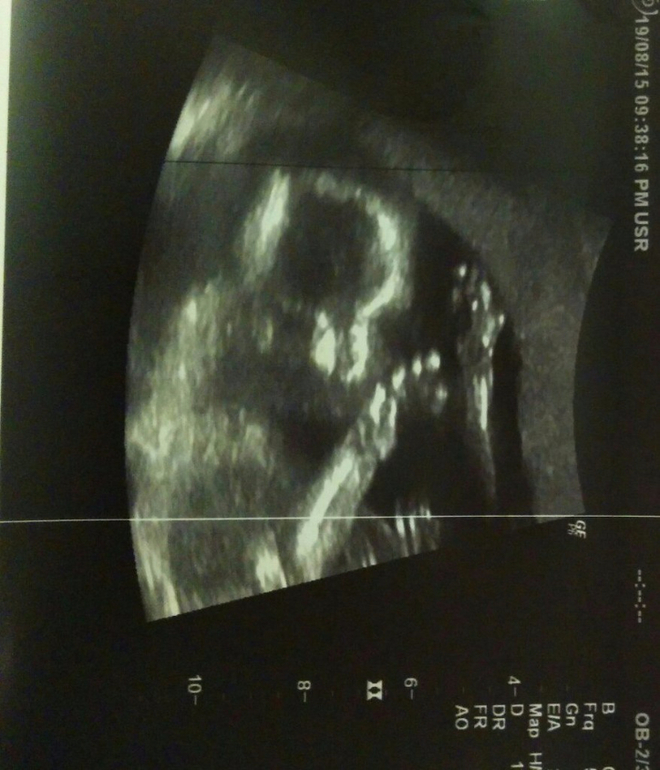

Итак вчера 19 августа 2015 года мы ходили на УЗИ. Я ели вытерпила, чтобы дождаться 17 недель и пойти узнать пол. Пол очень хотела узнать, хотя понимала, что могут и не сказать. Плюс очень хотела получить хорошие фото малыша. На память )

В общем она выключила свет, положила меня, немного повернула ко мне экран (в первое узи никому и дела не было, что я не вижу экран - я была очень расстроена). и начала все все подробно рассказывать и показывать. Мужу моему тоже показывала все, пальчиком по экрану водила, чтобы мы точно видели и понимали что и как. Мне в принципе была нужна одна хорошая фотография. А она видит что-то интересное и что я умиляюсь - и печатает. Сама ! я даже ей ничего не говорила !!! В итоге получилось аж 9 фотографий !!!! некоторые из них явно для врача (пуповина, шейка и все такое). но и она печатала, то что просила я.

В итоге она смотрела смотрела и насмотрела нам мальчика !!!!

В общем ребеночек у нас в порядке - соответствует сроку беременности. Врач не один раз сказала, что все хорошо - мы с мужем были очень рады )

Ниже фото

1. Лицо и ручки у лица